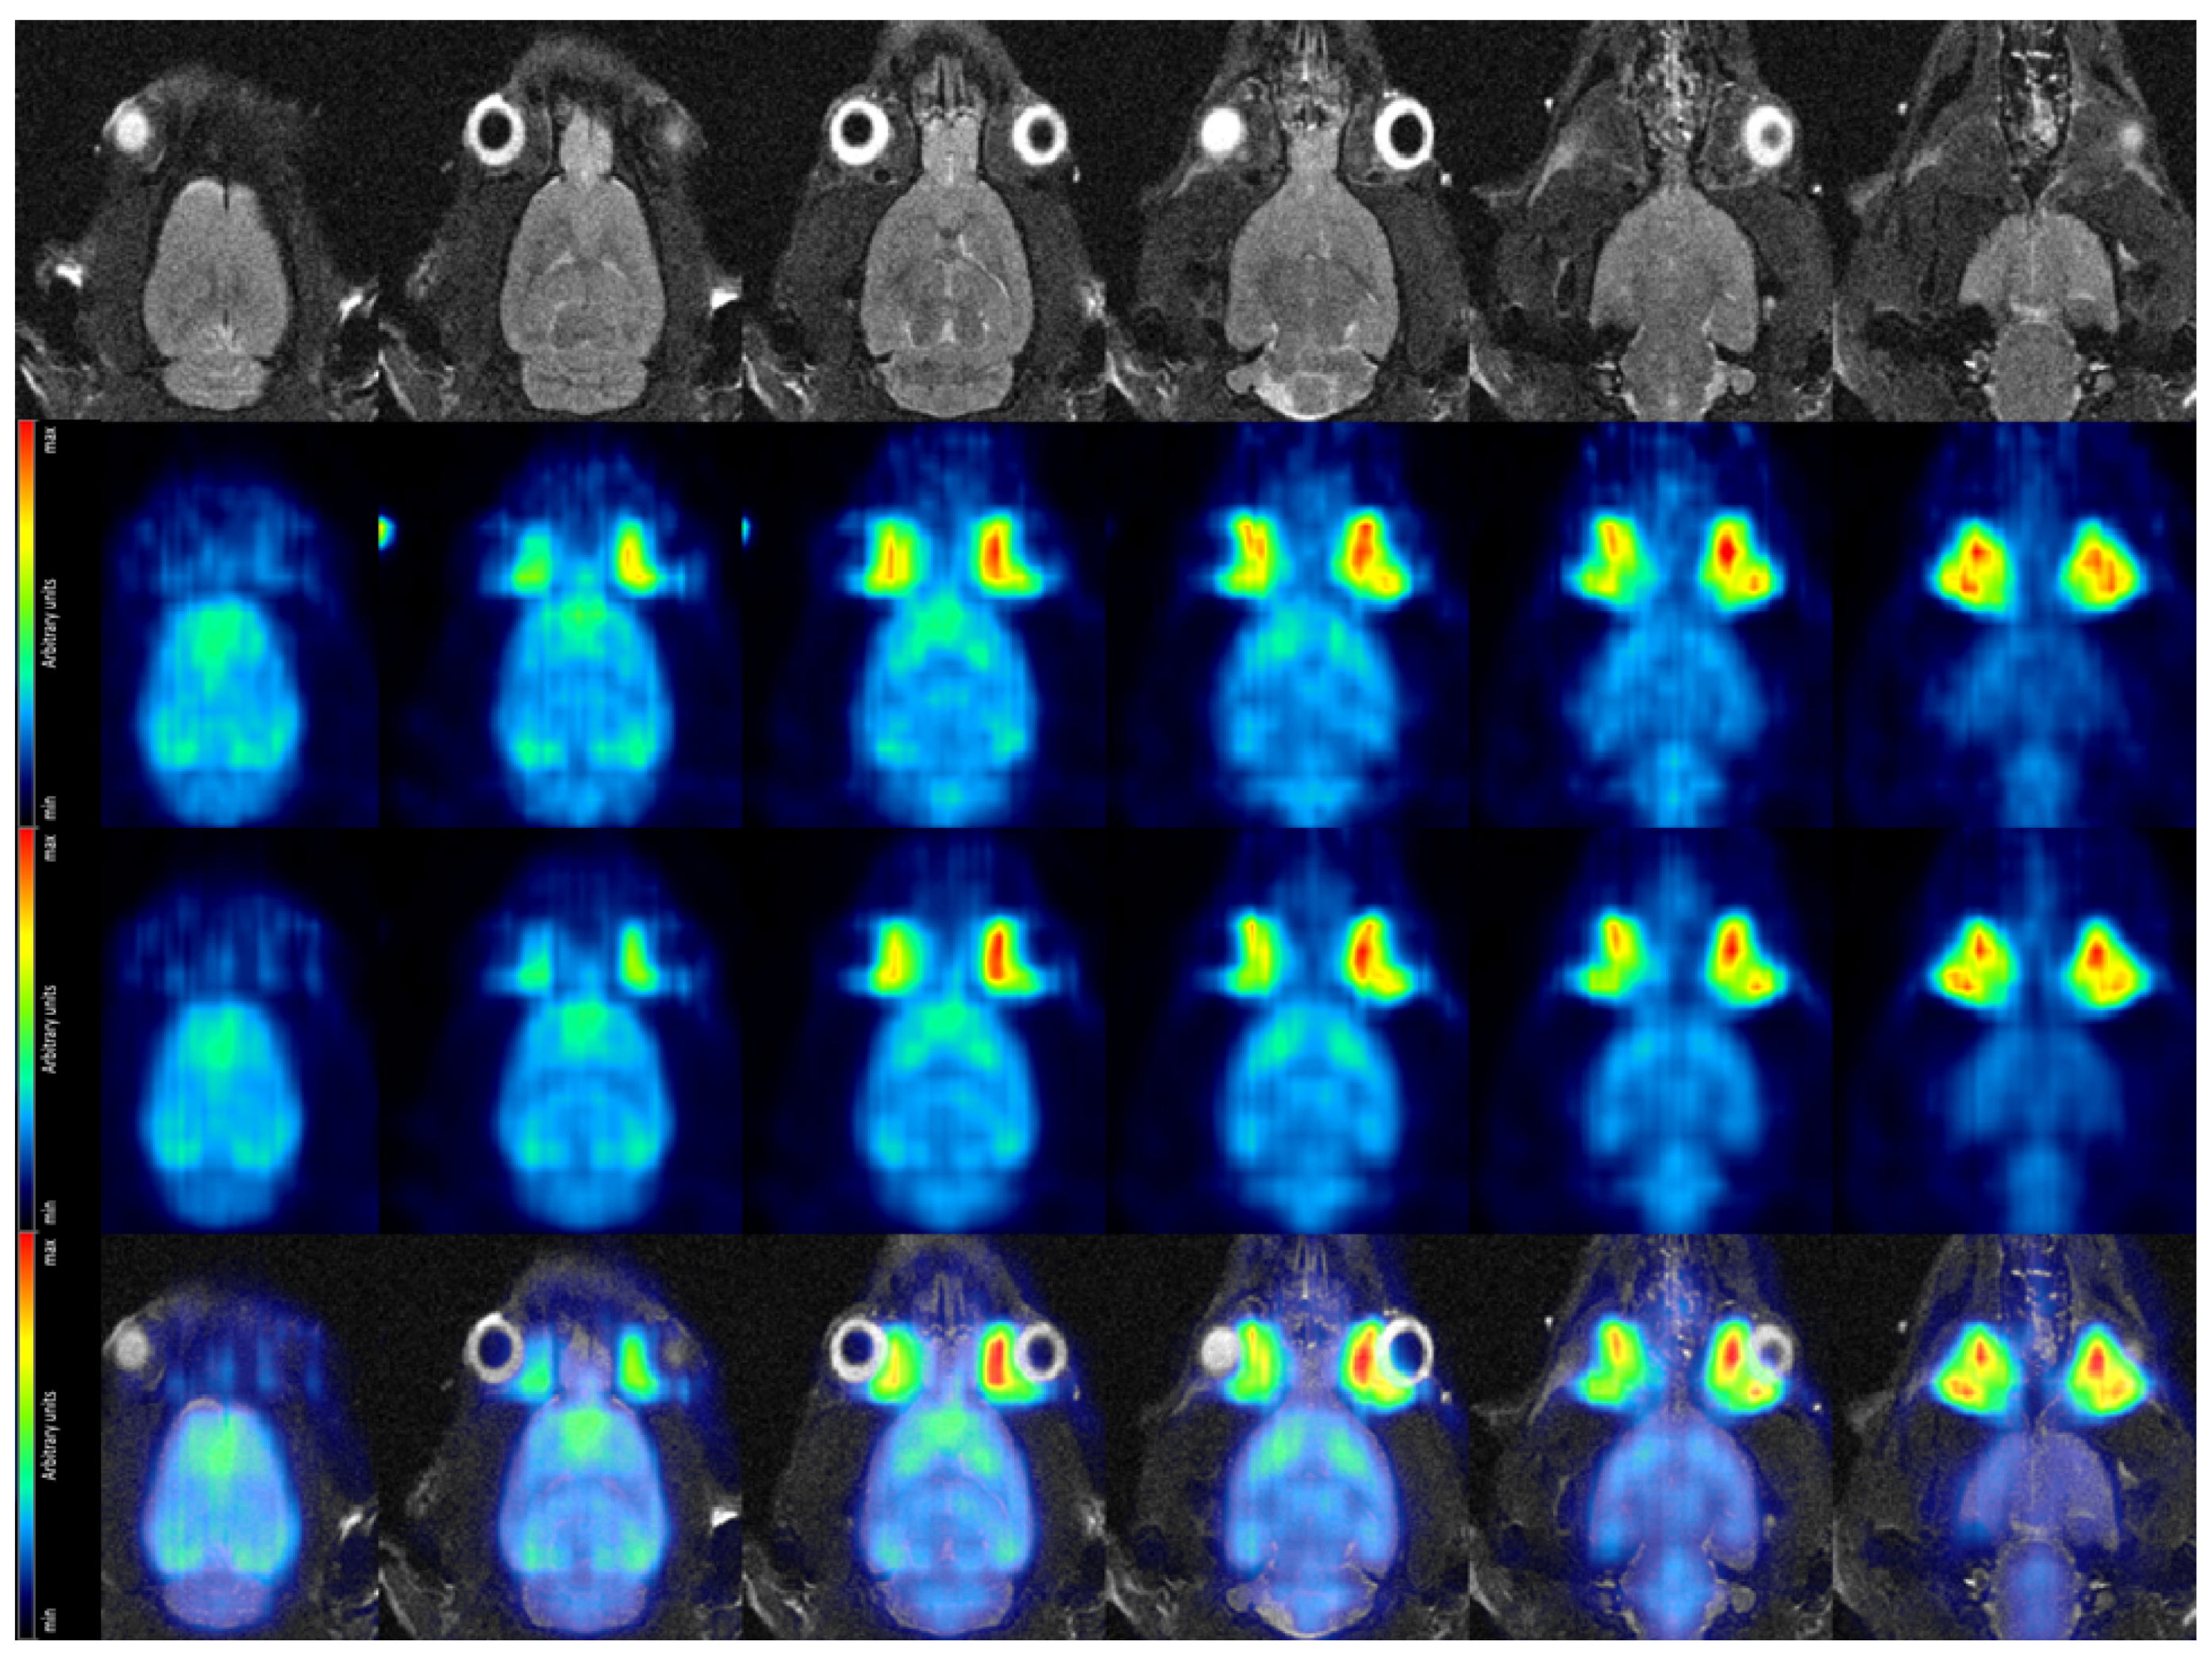

Figure 14 shows a selection of coronal view cuts of the rat brain for both high and low decay rate, the MR slices recorded with a T2-TurboRARE sequence serving as anatomical reference and finally the fused PET/MRI images (for the high decay rate measurement). Visualization of PET data and the fusion of PET and MR images were achieved using the software PMOD [44]. Particularly in the PET images acquired at high decay rate, the horseshoe-shaped cerebral cortex, which typically presents a thickness of 1.5–2.5 mm in rats [45], is clearly distinguishable.

Figure 14.

Coronal view of the rat brain in vivo. (Top row): MR images acquired with a T2-TurboRARE sequence. (Second row): PET data acquired at low dose. Average over frames 22–25, corresponding to 25–45 min after tracer injection. (Third row): PET data acquired at high dose. Average over frames 22–25, corresponding to 25–45 min after tracer injection. (Bottom row) Fused MRI and high dose PET data.

Summarizing the in vivo rat brain study, an improvement on image quality from the low to the high dose acquisition (second and third row of Figure 14) is apparent. The clearly discernible cerebral cortex demonstrates that we have achieved our targeted spatial resolution of ∼2 . Once we will have implemented data corrections to the reconstruction of SAFIR-I data and obtained a measurement with an appropriate calibration phantom, we will be able to quantify the image voxels and show Time-Activity Curves (TACs) for the rat’s cerebral cortex at both low and high decay rates.